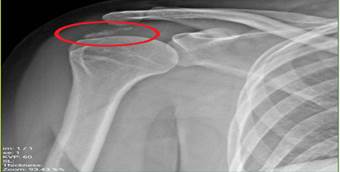

pain, which he described as VAS scores of 10/10. Imaging finding [X-ray]

revealed calcification within the subacromial space (Figure 1).

Figure

1.

Anteroposterior external rotation radiograph of the right shoulder,

demonstrating marked soft tissue calcifications identified at the insertion

site of the supraspinatus tendon.